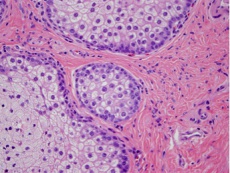

Histopathology

The histopathology varies depending on the differentiation of the tumor. In well differentiated lesions, there is a lobular arrangement and vacuolization of the cytoplasm cells centrally.

Cells present will include sebaceous and undifferentiated cells. There may be variation in nucleus shape and size with high mitotic activity indicated by mitotic figures. Special stains can be used to help distinguish sebaceous carcinoma: oil red-O, Sudan IV, epithelial membrane antigen, Leu-m1 immunostains. [1]

Below are examples of sebaceous carcinoma. The first image shows an eyelid margin with normal sebaceous glands at the inferior margin, the invasive sebaceous carcinoma, and a hair follicle in between. The 2nd and 3rd images are high power images of the carcinoma (with mitotic figures in deep purple) and normal sebaceous glands.